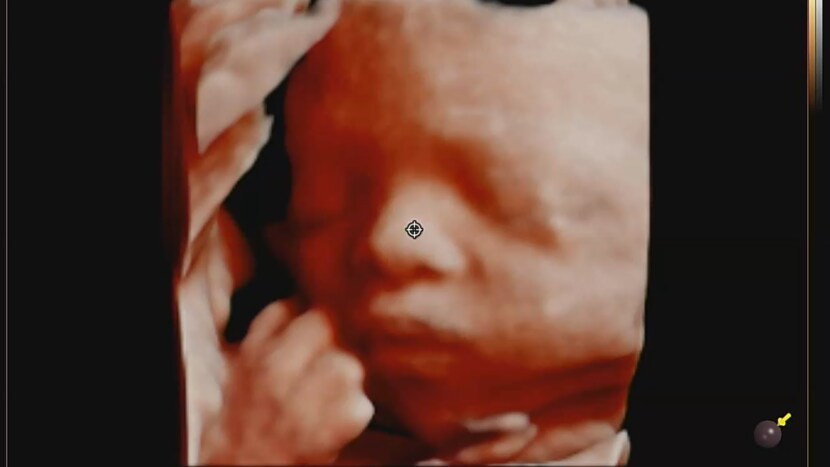

23.03.09 101 읽음 임신중기 4D초음파 스크럼프 구독하기 5 4 콘텐츠의 수익 3 어느덧 중기 후반 이네요 이제 제법 살이 붙어서 더 이뻐졌어요❤️주먹을 꼭 쥐고 잠든것 같죠?ㅋㅋ엄마랑 아빠랑 반반 닮은것 같아요포토샵?처럼 주변에 있는것 지워주시고여러 각도로 인화해 주시네요ㅋㅋ건강하게 만나자❤️ 4 0 / 300 입력